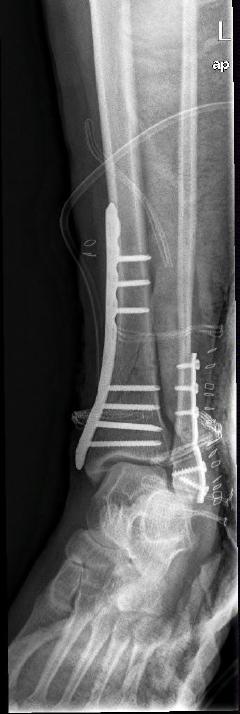

Κατάγματα μακρών οστών άνω και κάτω άκρου

Τα εν λόγω κατάγματα είναι αρκετά συνηθισμένα και συχνά συμβαίνουν μετά από τροχαία ατυχήματα ή πτώση από ύψος. Παρατηρείται εξαιρετικά μεγάλη ποικιλία στη μορφή τους, κατα κανόνα όμως είναι σοβαρά και πολλές φορές ανοικτά – δηλ με τραύμα στο σημείο του κατάγματος – κάτι που αυξάνει τον κίνδυνο λοίμωξης και επιβαρύνει την πορεία της θεραπείας. Στα κατάγματα των άνω άκρων ενδέχεται να υπάρξει και τραυματισμός νεύρων, που χρειάζεται επίσης αντιμετώπιση.

Με τα σύγχρονα μέσα που διαθέτουμε, όλα σχεδόν αυτά τα κατάγματα πρέπει να αντιμετωπίζονται χειρουργικώς. Υπάρχει πληθώρα υλικών οστεοσύνθεσης (πλάκες διαφόρων τύπων, ενδομυελικοί ήλοι, συστήματα εξωτερικής οστεοσύνθεσης) που είναι διαθέσιμα και επαφίεται στην εμπειρία του χειρουργού η επιλογή.

Οπως και άλλοι εξοικειωμένοι χειρουργοί διεθνώς, χρησιμοποιώ τεχνικές ελάχιστης παρέμβασης (Minimal Invasive Surgery), δηλαδή μικρές τομές, επειδή έτσι το χειρουργικό τραύμα είναι ελάχιστο, με αποτέλεσμα ταχύτερη επούλωση. Ταχύτερη πώρωση των καταγμάτων, ταχύτερη κινητοποίηση.

Περίπτωση 4ου ασθενούς